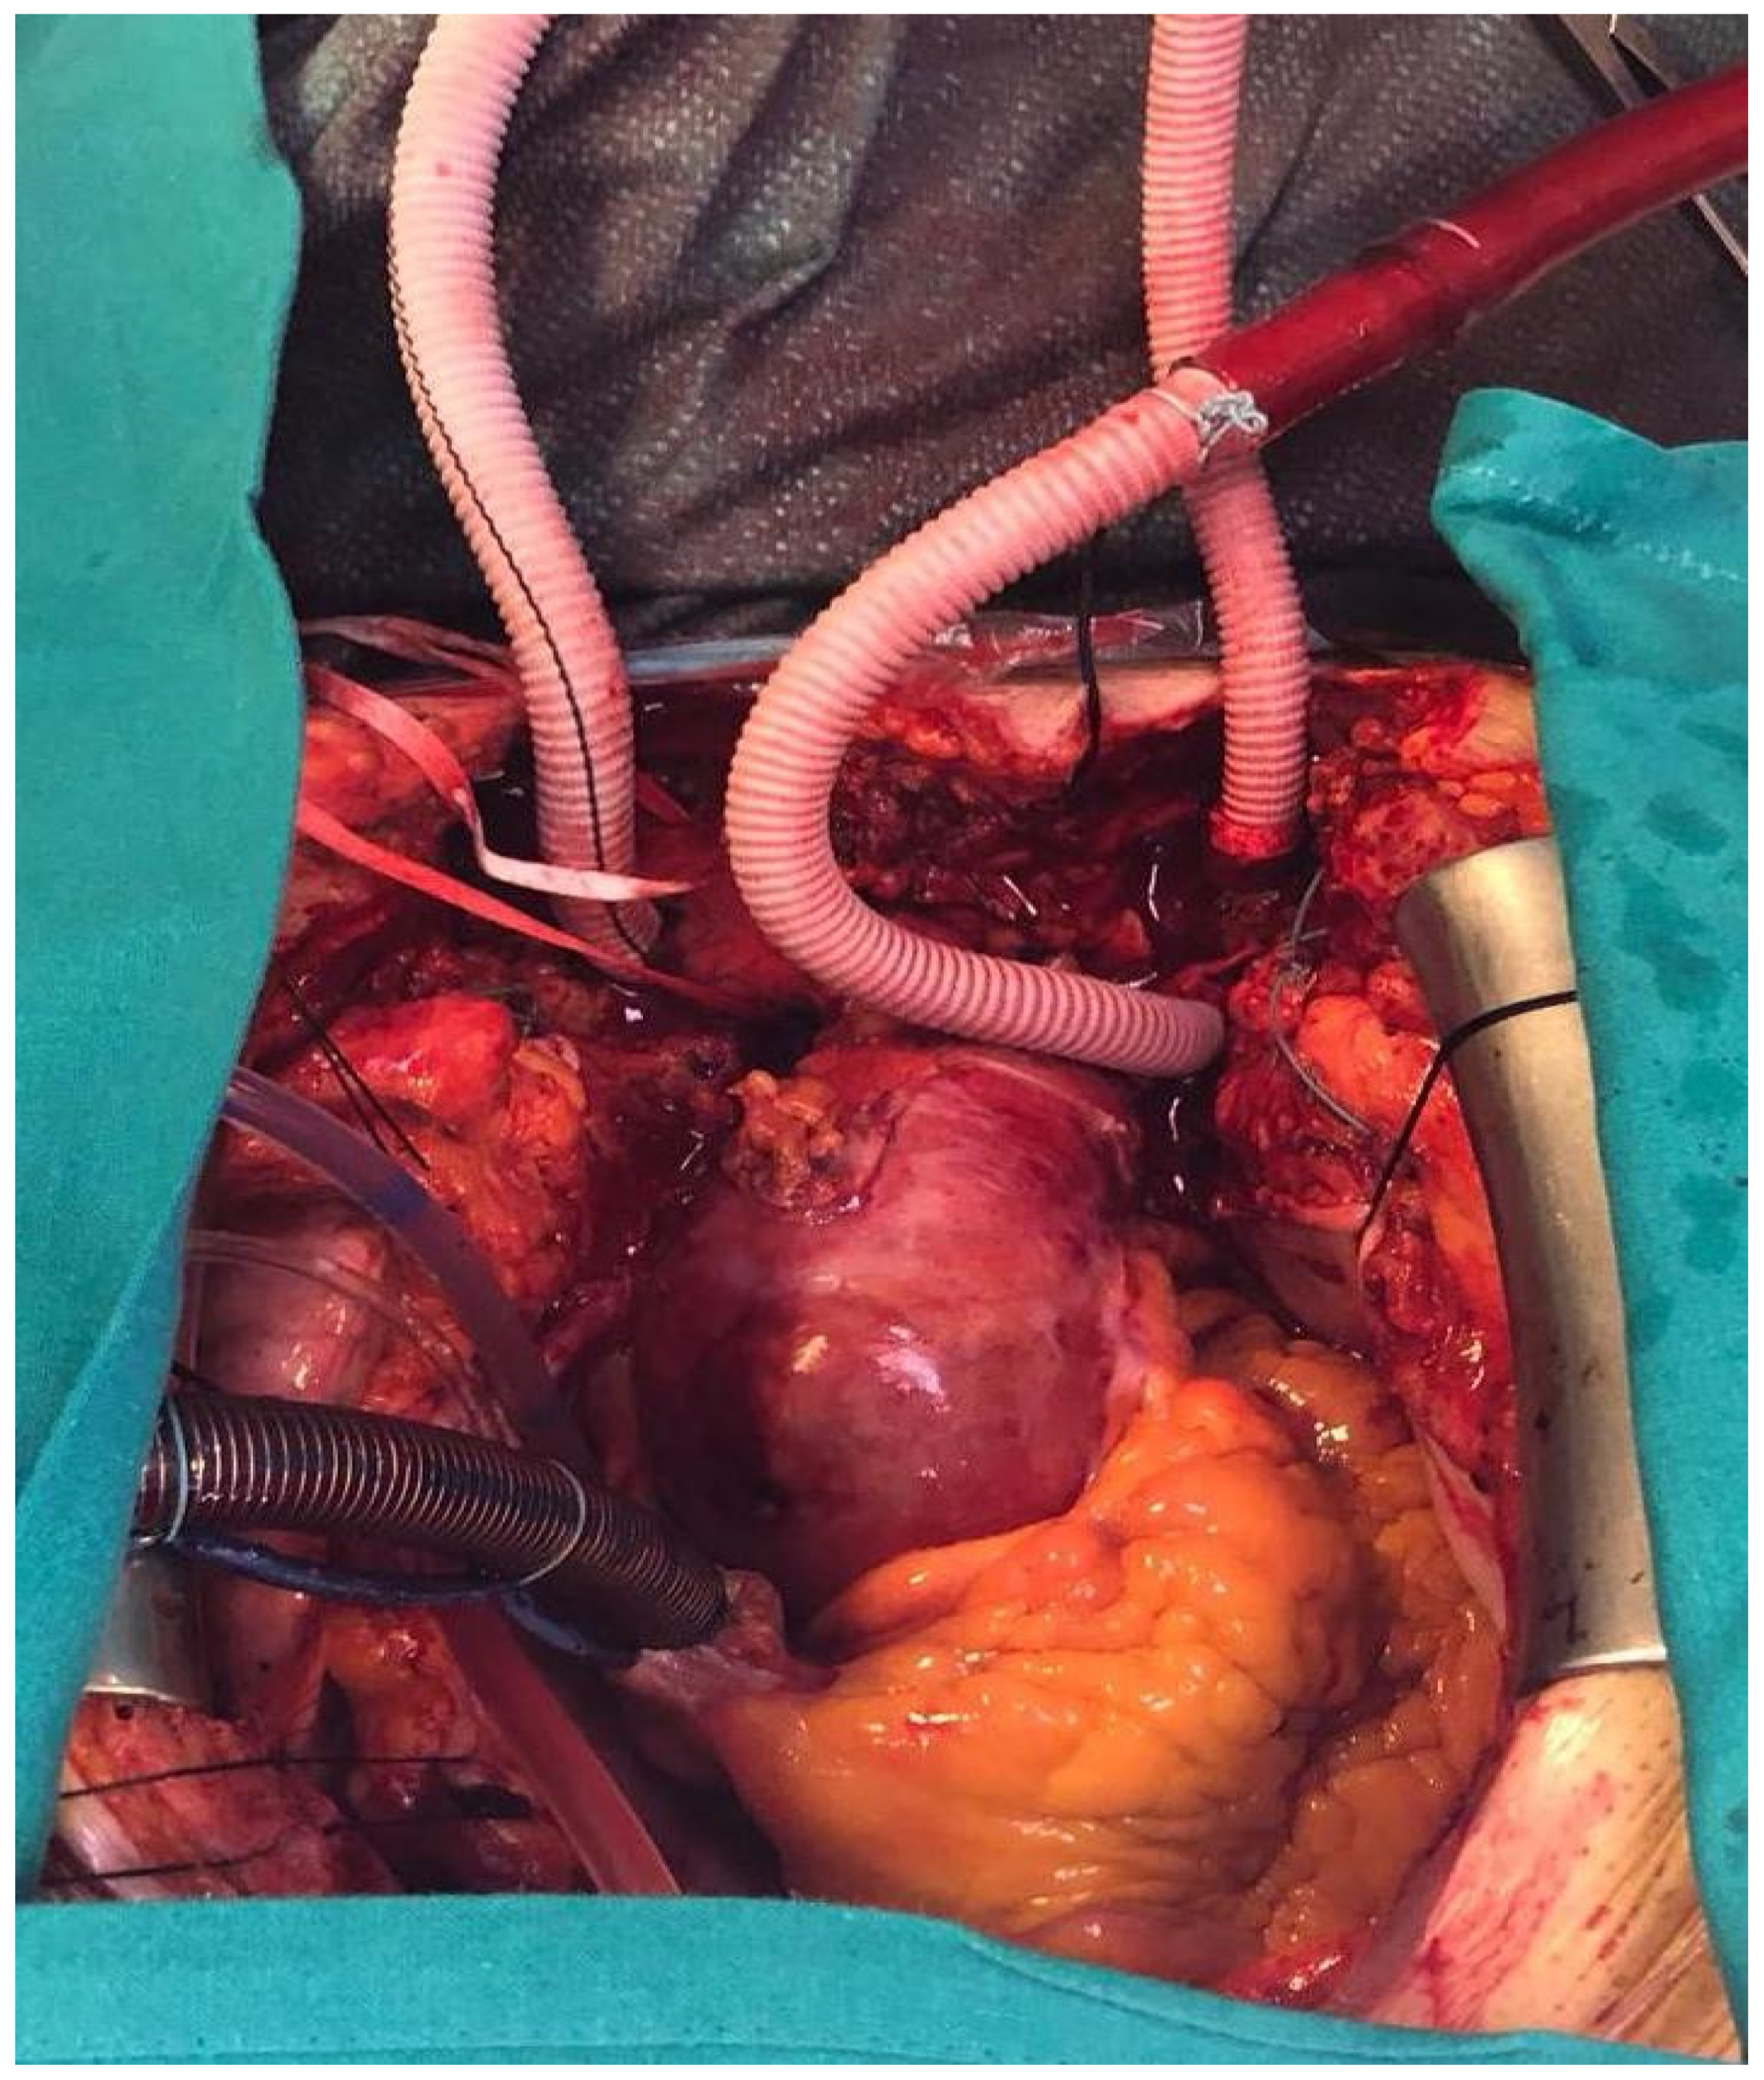

2. Preoperative Considerations and Surgical Procedure

3. Cannulation Strategy